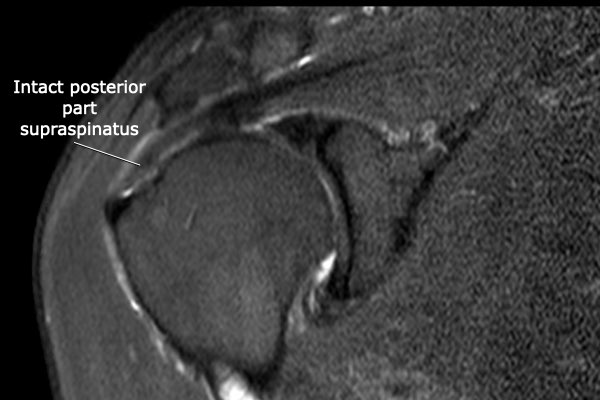

Có hình ảnh rách toàn bộ chiều dày phần trước của gân cơ trên gai, kéo dài từ mặt khớp đến mặt túi hoạt dịch.

Do các sợi gân phía sau của gân cơ trên gai còn nguyên vẹn, tổn thương này được gọi là rách toàn bộ chiều dày không hoàn toàn của gân cơ trên gai.

Không có co rút.